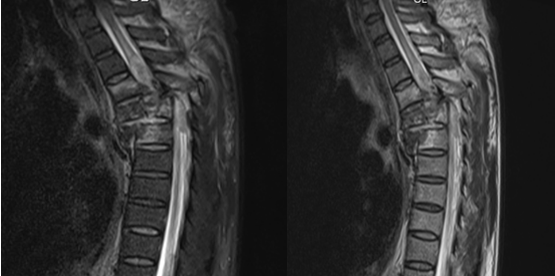

脊柱转移瘤胸椎

脊柱转移瘤胸椎,脊柱转移瘤

脊柱转移瘤

脊柱转移瘤图片

转移性脊柱肿瘤图片

脊柱转移瘤磁共振图片